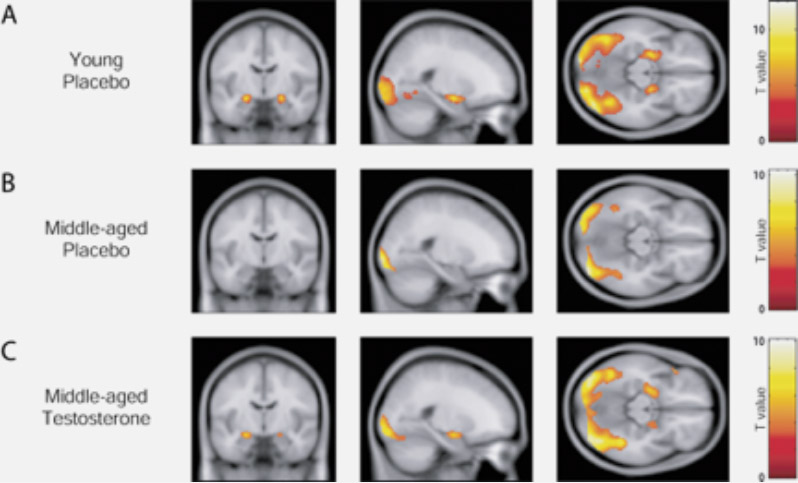

A clinical study using the MetP technology for targeting the human brain:

Consider the amygdala reactivity after a single nasal administration of testosterone.

Van Wingen et al.: «The middle-aged women received a single nasal dose of testosterone in a double-blind, placebo-controlled, crossover manner, which rapidly increased amygdala reactivity to a level comparable to the young women.»